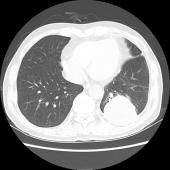

性别:男,年龄:60岁,患者1年半前因咳嗽于当地医院查胸部CT示左肺下叶占位,行抗感染及对症治疗后症状缓解,未复查。半月余前出现发热,体温最高37.5℃,伴咳嗽,咳少量白色偶有黄色粘痰,左侧胸痛。

左肺下叶可见高密度肿块影,边界清晰,边缘不规则,左肺下叶支气管局部截断,增强后病灶边缘轻度强化,中心未见明显强化;左侧胸腔内可见液性密度影;纵隔内未见明确肿大淋巴结影。

(左下叶)肺肉瘤样癌(巨细胞癌),伴大片坏死

肺肉瘤样癌是一种少见的非小细胞肺癌,WHO将其分为5个亚型:多形性癌、梭形细胞癌、具巨细胞癌、癌肉瘤和肺肉瘤。主要见于老年患者,男多于女,临床症状与肿瘤生长部位及侵犯周围组织的情况有关,中央型较易侵犯支气管,症状往往出现较早。CT多表现为肺内单发肿块影,最大径一般大于5cm,周围型多于中央型,可跨叶生长;边缘光滑或清晰;毛刺征及胸膜牵拉症少见;坏死、空腔及分叶、支气管截断多见,坏死边界不清,可见坏死内强化灶,肺门及纵隔淋巴结转移多为环形强化。需要鉴别以下几种疾病:肺结核球呈圆形或类圆形,多数密度不均匀,周边或中央常可见钙化,病灶中心有时可见小空洞。病灶边缘清楚,部分边缘可呈浅分叶状,少数可见毛刺征或胸膜凹陷征,周围常可见卫星灶。增强检查病灶不强化或仅轻度强化。周围型错构瘤直径多在2.5cm以下,瘤体内可见斑点状或爆米花状钙化,部分病变有脂肪密度,多数病变边缘清楚、光滑,CT增强大多数病灶无明显强化。肺炎性假瘤呈圆形或类圆形高密度影,密度较均匀,边缘多清楚而光滑,少数可呈毛刺样改变,增强检查大多数肿块较显著均匀强化。